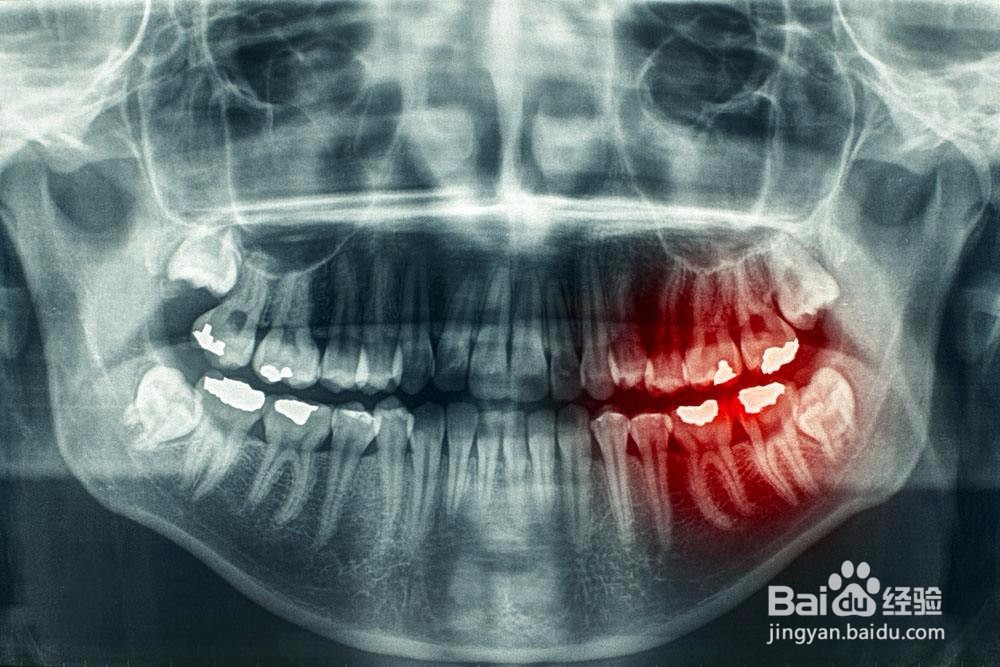

2、第五,如果你不是很痛,想自己先了解一下的话,可以自己先去医院拍个片子,看看自己的智齿是不是到了必须要拔的程度。